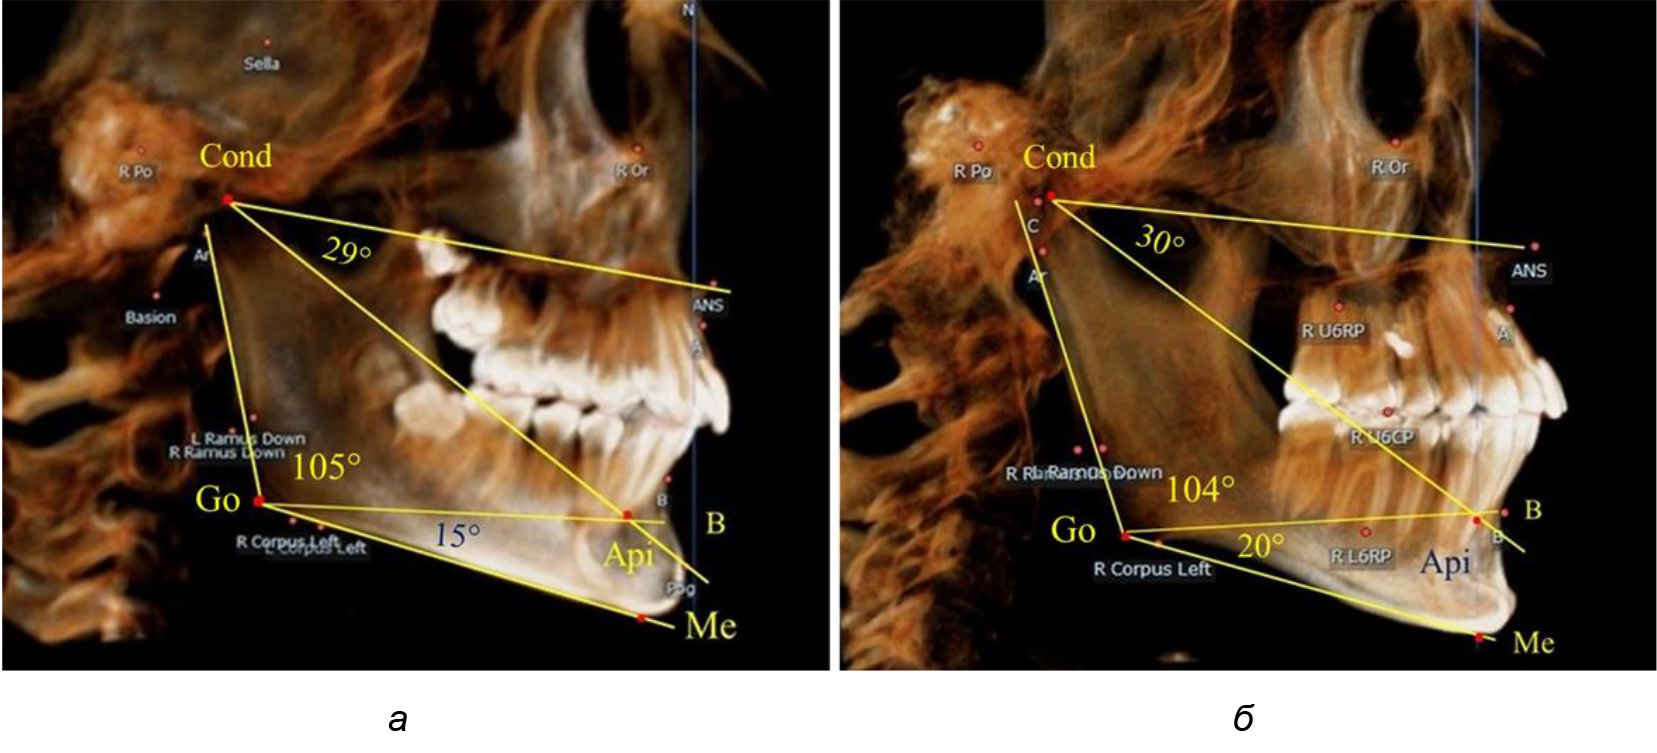

После смены всех молочных зубов (анализ 9 ТРГ) и после прорезывания вторых постоянных моляров (7 человек) происходил очередной этап подъема высоты прикуса с увеличением размеров костей гнатической части лица. Однако величина основного угла гнатической части лица SNA-Cond-Api, так же как в молочном и сменном прикусе, в норме составляла (30,02 ± 1,25)°, что не имело достоверных различий (р ˃ 0,05) с аналогичным параметром, анализируемом в других группах исследования. Угол нижней челюсти и его составляющие отличались вариабельностью параметров при различных показателях нижнечелюстного угла (рис. 6).

Рис. 6. Варианты 3D рентгенограмм детей после смены всех молочных зубов (а) и после прорезывания вторых моляров (б)